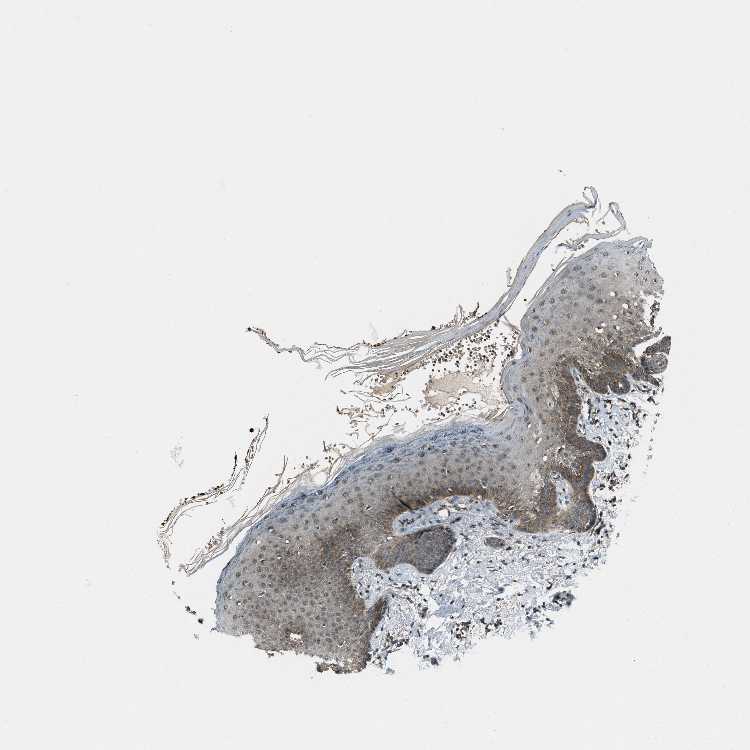

TISSUE PRIMARY DATA SKIN Show tissue menu

SKIN 1 - Antibody stainingi

Antibody staining in the annotated cell types in the current human tissue is reported as not detected, low, medium, or high, based on conventional immunohistochemistry profiling in selected tissues. This score is based on the combination of the staining intensity and fraction of stained cells.

Each image is clickable and will lead to virtual microscopy that enables deeper exploration of all samples and also displays staining intensity scores, fraction scores and subcellular localization as well as patient and tissue information for each sample.

Antibody HPA020095Antibody HPA020138Antibody CAB010878Antibody CAB080402

Langerhans MediumMediumNot detectedNot detected

Fibroblasts MediumNot detectedLowNot detected

Keratinocytes MediumMediumLowHigh

Melanocytes MediumMediumLowNot detected

SKIN 2 - Antibody stainingi

Epidermal cells LowMediumMediumMedium